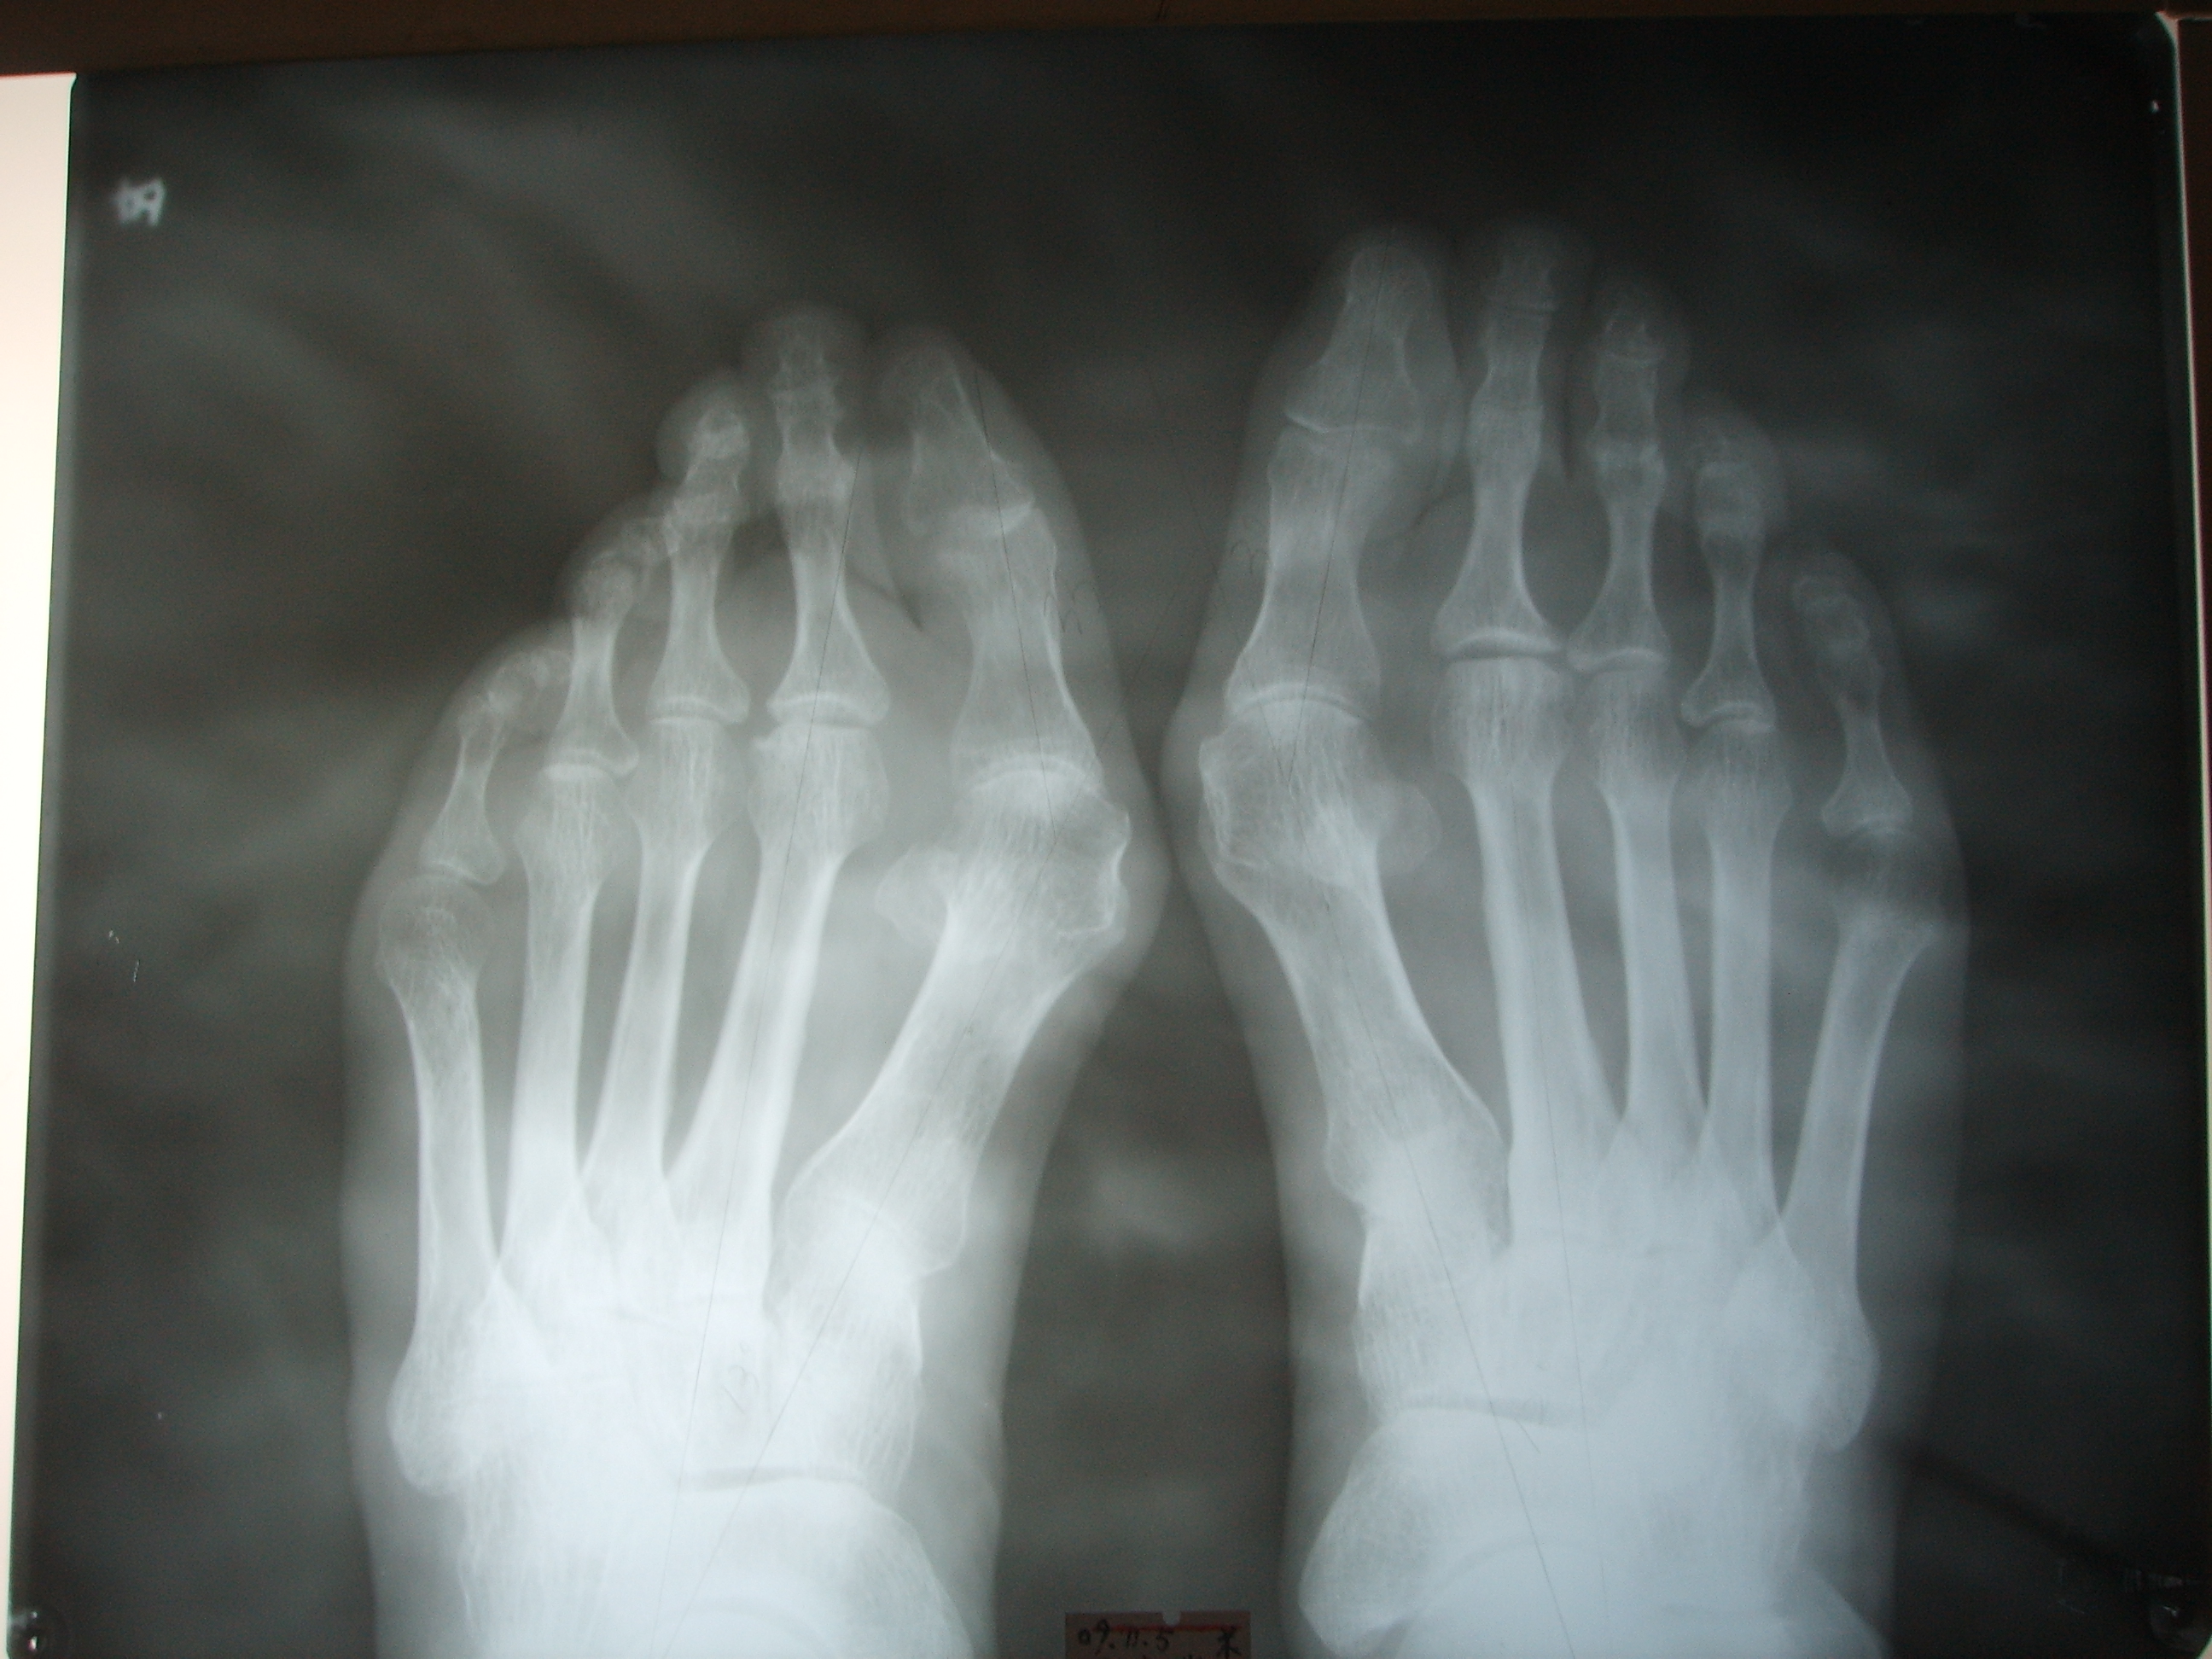

从这个大姐的片子可以看到,她的第一跖趾关节有点骨关节炎,关节间隙很窄了,第二跖骨干和跖骨头都有明显的代偿性增粗,双足第五跖骨头明显增粗,我们检查发现,前足足横弓塌陷明显,双足的第一趾骨也明显偏斜,这个按理需要同时做个截骨,但是沟通过程她不同意,担心特别疼,要求只要感觉局部凸起,拇趾后续稍微偏一点问题不大,也就只做了第一跖骨截骨矫正。